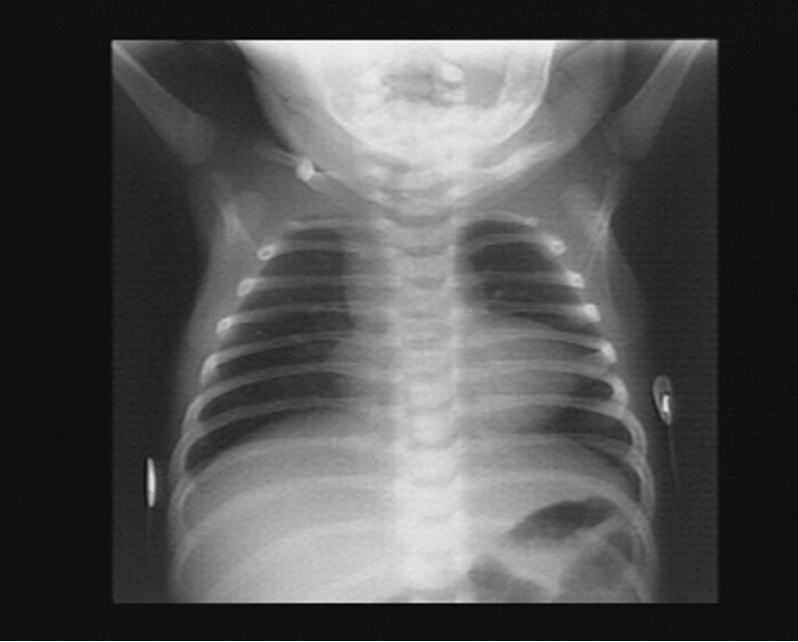

- A chest radiograph: cardiomegaly, narrow mediastinum, and increased pulmonary vasculature. ECG: RAD and RVH